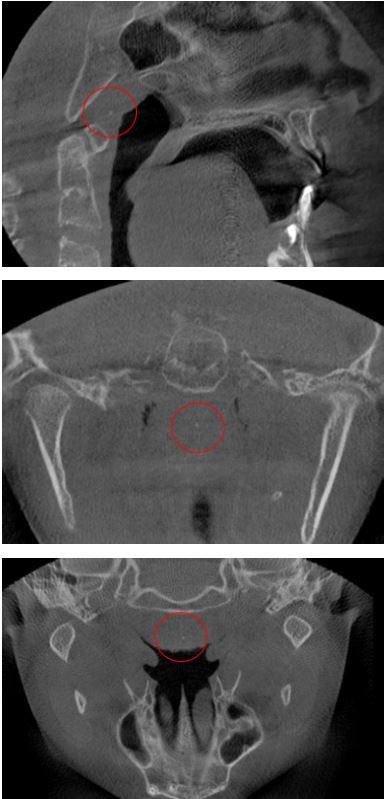

Los tonsilolitos encontrados afectaron, principalmente, a las amígdalas palatinas (figura 1), con un 96,8 % (n = 120); a las amígdalas linguales (figura 2), con un 2,4 % (n = 3); y, finalmente, a las amígdalas nasofaríngeas (figura 3), con un 0,8 % (n = 1) (tabla 10).

Imágenes tomadas del archivo del Servicio de Radiología Bucal y Maxilofacial del CDD-UPCH (sede San Isidro)

Los tonsilolitos fueron encontrados principalmente en la amígdala palatina, en un 96,77 % (n = 120); seguido de la amígdala lingual, en un 2,42 % (n = 3); de las amígdalas nasofaríngeas, 0,81% (n = 1); y finalmente no se encontraron tonsilolitos en las amígdalas tubáricas. Ello coincide con distintos informes (8,10,11), que muestran que los tonsilolitos palatinos son uno de los hallazgos más comunes entre las calcificaciones patológicas en la región de la cabeza y el cuello, oscilando entre el 16 % y el 46,1 %. La alta prevalencia de tonsilolitos en las amígdalas palatinas podría deberse a que estas presentan criptas más profundas, ramificadas y relativamente apretadas. Las amígdalas linguales presentan criptas poco aplanadas, poco ramificadas, bastante separadas unas de otras. Las amígdalas faríngeas y tubáricas no presentan criptas típicas sino pliegues con recesos irregulares. Además, las amígdalas palatinas suelen estar más expuestas a las infecciones crónicas recurrentes, al tabaquismo, a las bebidas alcohólicas y a la mala higiene en comparación con las amígdalas linguales nasofaríngeas (12,15).